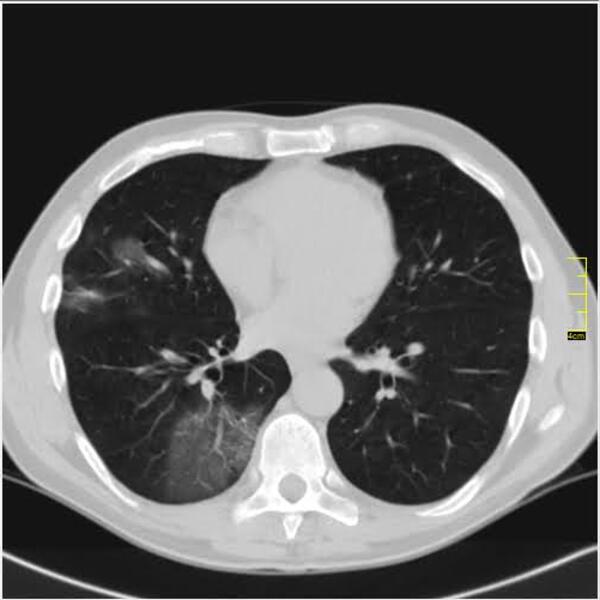

Decembar i januar je dominirao britanski soj. Kada se pogledaju njegove slike vidi se razlika u odnosu na divlji a blizu je onoga koji je bio u leto 2020. godine.

Decembar, januar, februar, mart. 2020/21.

Gustina promena je različita, razlikovala se i klinička slika. retko u decembru ali do marta skoro isključiv.